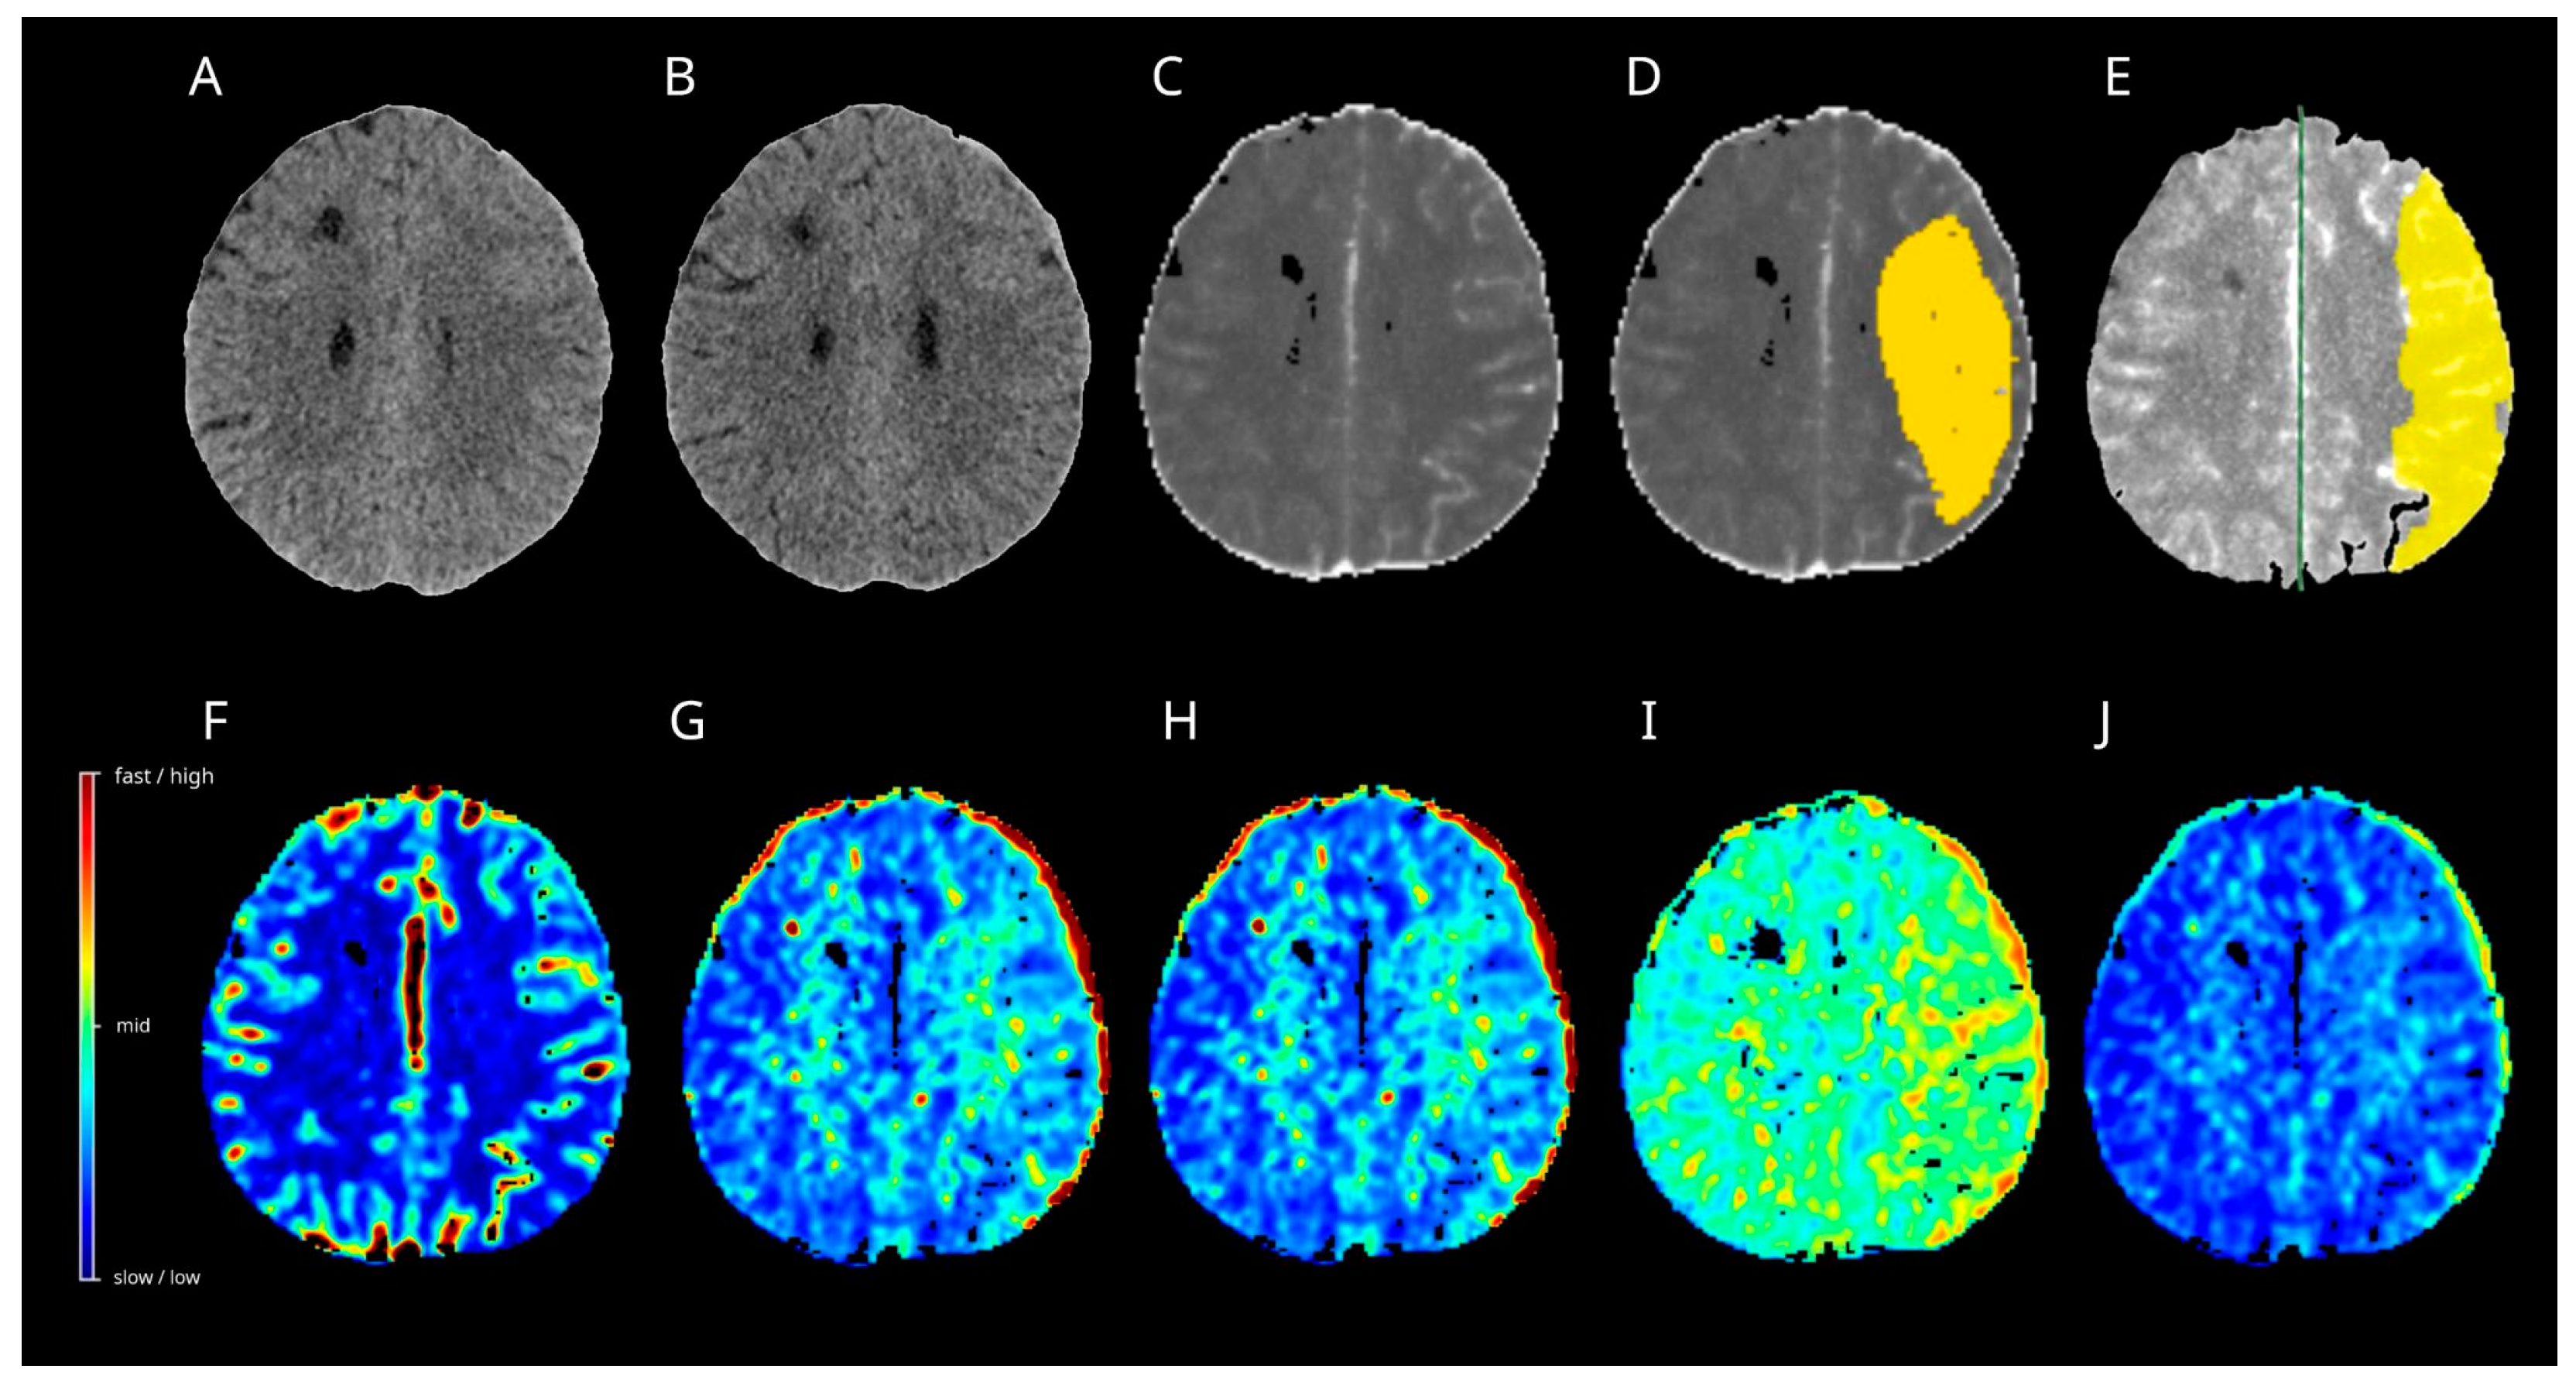

3.10. Case 1

3.11. Case 2